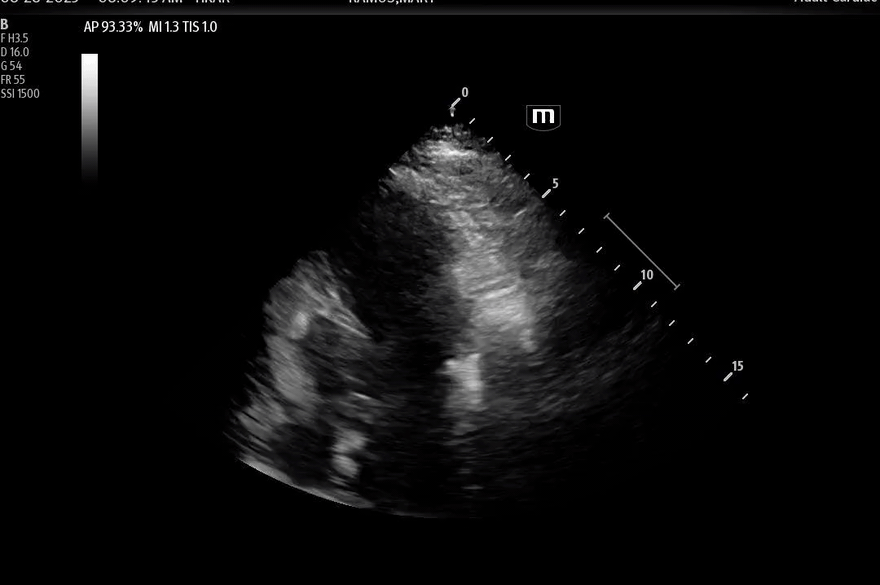

Bedside POCUS

• There was inferolateral wall motion abnormality, basal hypercontractility, apical ballooning

• No pericardial effusion.

Here are the POCUS images:

• This POCUS finding may also be described as systolic apical ballooning of the LV with hyperkinesis of the basal walls. Of note, there are also less common regional wall motion abnormalities seen.